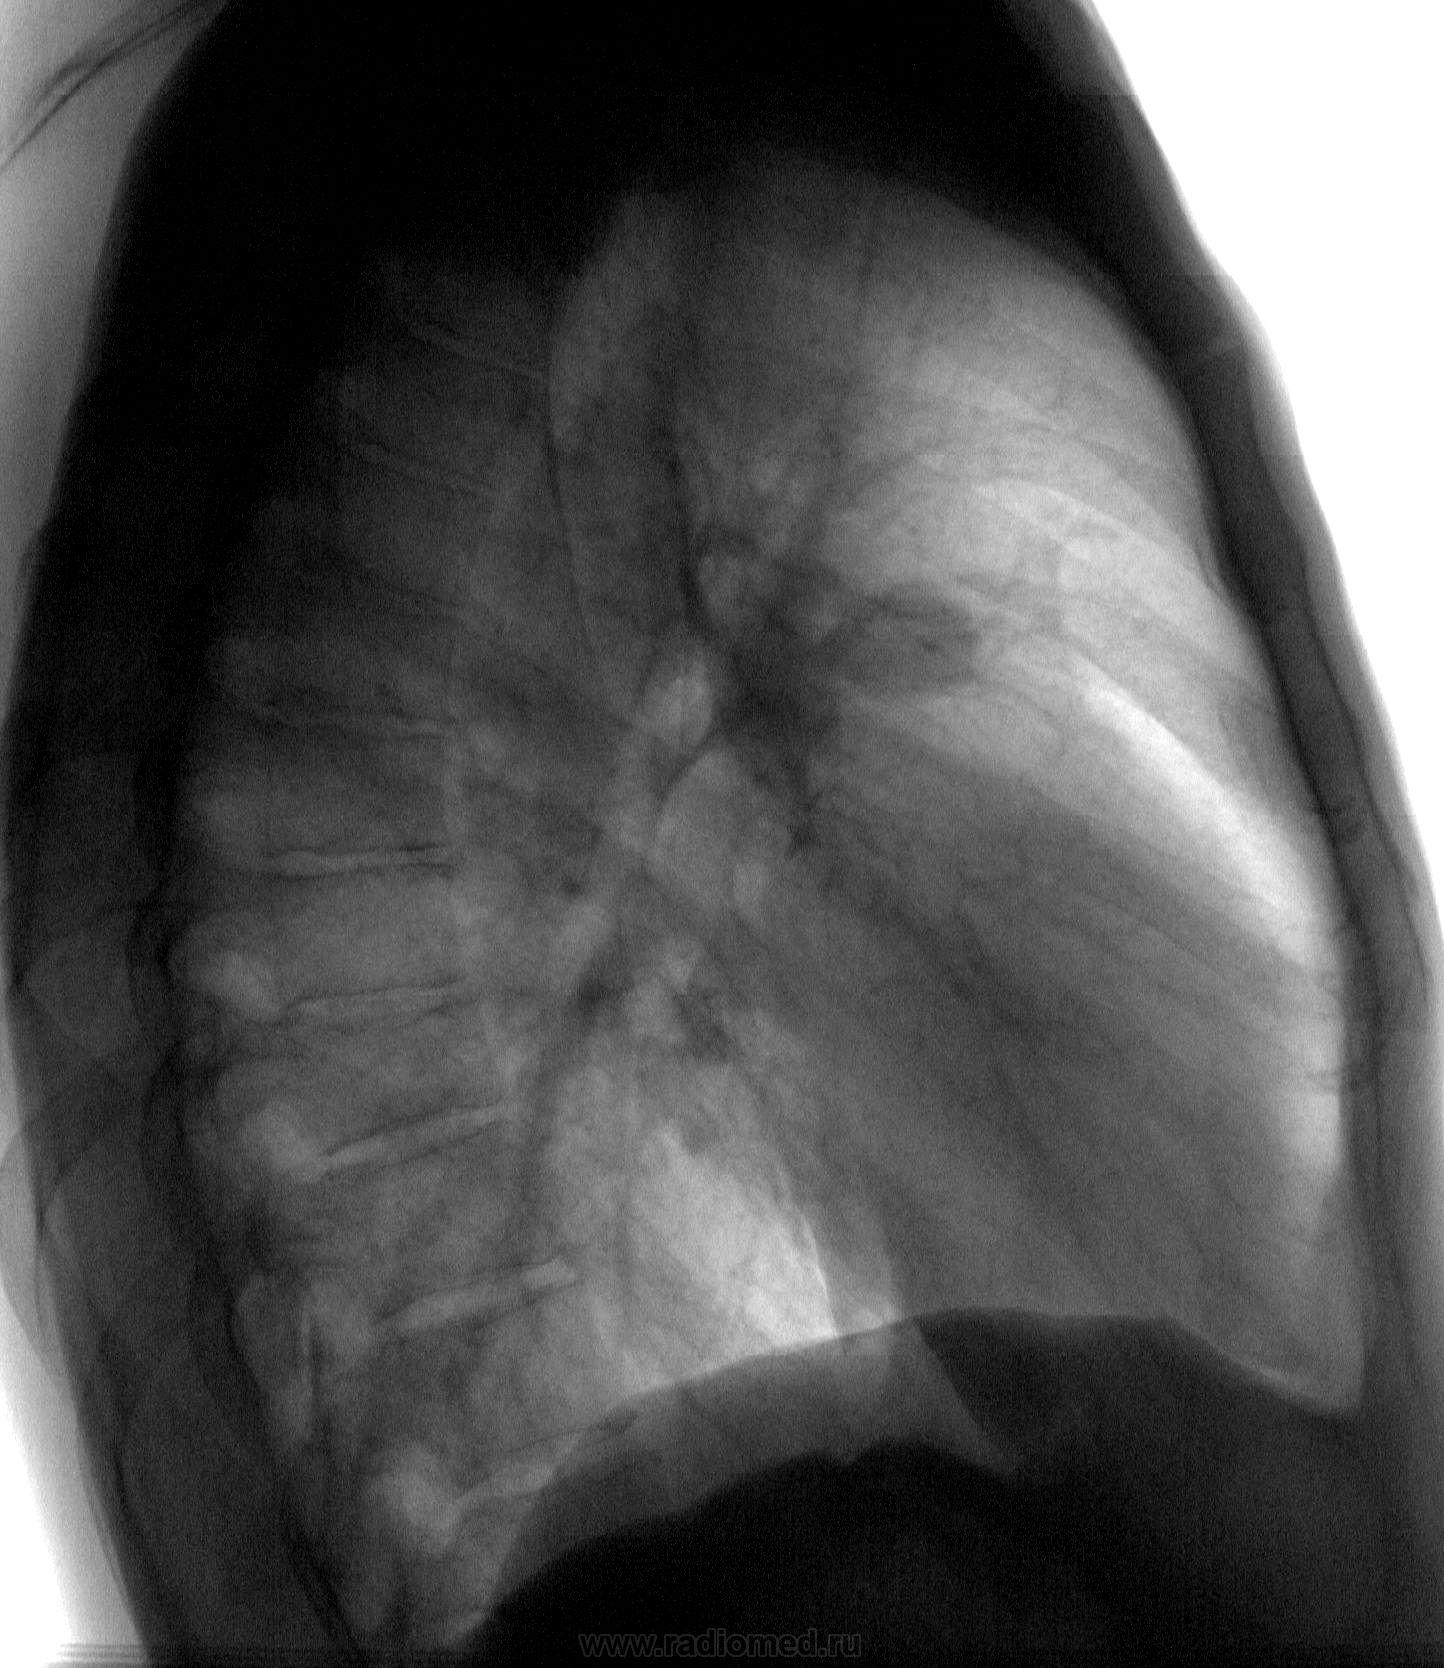

Бомжеватого вида молодой человек, вспомнив о двух детках, решил устроиться на работу, требует положительной флгр. Жалоб не предъявляет, архива нет. Предыдущая Ro-гр.ОГК - 2 года назад в наркодиспансере, где выходил из запоя. По его словам - было все ОК. Что-то есть справа в S1. А что это за гомогенноинтенсивночеткий кругляшок, да еще (если пофантазировать) с дренажным сосудиком? Какая-то киста, или что-то посерьезней. Если допустить, что на верхушке фиброзноочаговые изм., а второе - киста - можно и отпустить с богом. Все равно (по его словам) денег на КТ ОГК, консультации (особенно в онко) нет. Пожалеть деток?

Не внушает мне эта тень «фейсно», как отражение периферического рака, никакого доверия и симпатии.